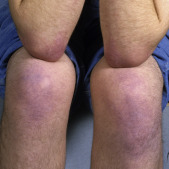

Physical Examination

- •

Cutaneous: livedo reticularis ( Fig. 3.27 ) , cutaneous necrosis, skin ulcerations ( Fig. 3.28 ), gangrene of digits

FIG. 3.27

Bluish, netlike, reticular pattern of discoloration involving the lower extremities associated with circulating antiphospholipid antibodies in this patient.

FIG. 3.28

Lacelike appearance of the skin with blue mottling in this patient with an ulcer due to infarction.

(Fitzsimons Army Medical Center Collection)